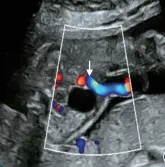

7.单脐动脉

单脐动脉指胎儿脐带内仅有1根脐动脉和1根脐静脉(正常由2根脐动脉和1根脐静脉组成)。

单脐动脉胎儿约30%合并其他结构畸形,如心血管、泌尿生殖系统、骨骼系统、神经系统和胃肠道等畸形。

需进行详细的结构检查,预后取决于合并畸形的严重程度。如果单脐动脉合并其他畸形或胎儿生长受限,应进行介入性产前诊断。